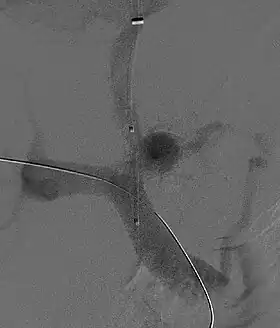

Fluoroscopic image of TIPS in progress. A catheter has been passed into the hepatic vein and after needle puncture, a guidewire was passed into a portal vein branch. The tract was dilated with a balloon, and contrast injected. A self-expandable metallic stent has yet to be placed over the wire.

Transjugular intrahepatic portosystemic shunts are typically placed by an interventional radiologist under fluoroscopic guidance.[9] Access to the liver is gained, as the name 'transjugular' suggests, via the internal jugular vein in the neck. Once access to the jugular vein is confirmed, a guidewire and introducer sheath are typically placed to facilitate the shunt's placement. This enables the interventional radiologist to gain access to the patient's hepatic vein by traveling from the superior vena cava into the inferior vena cava and finally the hepatic vein. Once the catheter is in the hepatic vein, a wedge pressure is obtained to calculate the pressure gradient in the liver. Following this, carbon dioxide is injected to locate the portal vein. Then, a special needle known as a Colapinto is advanced through the liver parenchyma to connect the hepatic vein to the large portal vein, near the center of the liver. The channel for the shunt is next created by inflating an angioplasty balloon within the liver along the tract created by the needle. The shunt is completed by placing a special mesh tube known as a stent or endograft to maintain the tract between the higher-pressure portal vein and the lower-pressure hepatic vein. After the procedure, fluoroscopic images are made to show placement. Pressure in the portal vein and inferior vena cava are often measured.